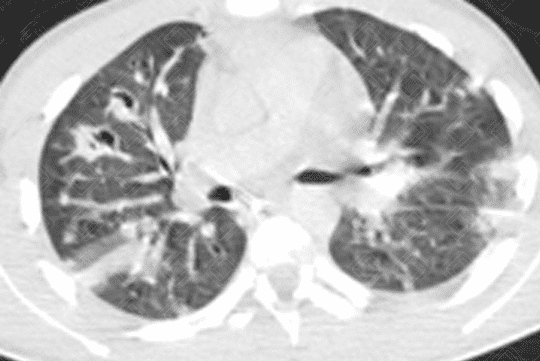

Descrição da lesão: Tomografia computadorizada do tórax (imagem axial e reformatação coronal) demonstrando opacidades nodulares bilaterais, esparsas e predominantemente periféricas, em vários estágios de escavação (setas vermelhas).

• Tomografia computadorizada do tórax: Nódulos em diferentes estágios de escavação, sendo mais numerosos na periferia dos pulmões e nos lobos inferiores. Podem ser observadas ainda consolidações geralmente subpleurais e cuneiformes.